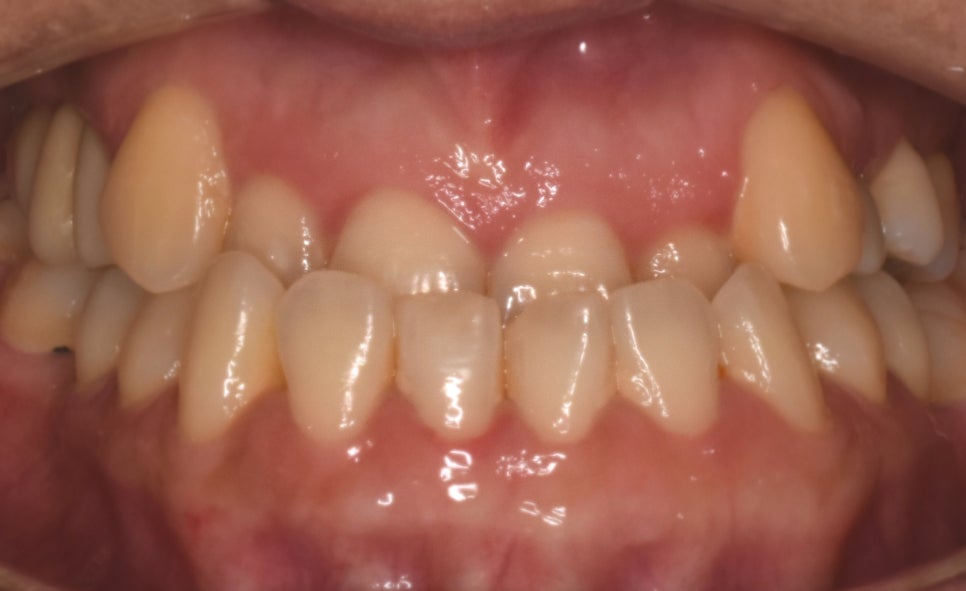

반대교합은 입을 다물었을 때

아래 앞니가 위 앞니를 덮는

'거꾸로 물리는 교합 관계'를 의미합니다.

🔎 교정시작 나이 : 24세

🔎 교정시작 이유 : 반대교합, 치아 벌어짐

🔎 교정 소요일 : 약 1년 2개월

앞니 반대교합

아래턱 돌출

치아 벌어짐

또한 치아배열도 좋지 않았고

비대칭이 함께 있는 상태였습니다.

반대교합과 불규칙한 치아배열,

아래턱 돌출 등의 문제사항이

확연히 개선된 것을 알 수 있습니다.